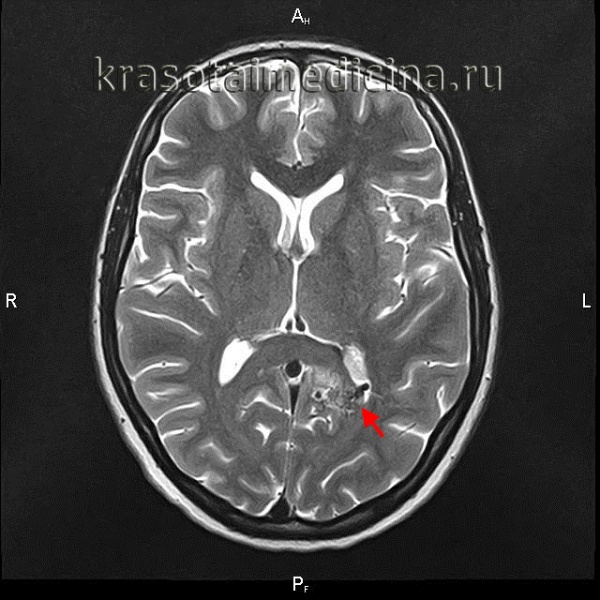

(Слева) Сагиттальный срез, Т1-ВИ: типичная картина КМ спинного мозга. На уровне С2-СЗ определяется неоднородное, несколько экспансивное интрамедуллярное образование. Виден характерный рисунок, напоминающий «соль с перцем», являющийся следствием повторных кровоизлияний и накопления ге-мосидерина.

(Справа) На сагиттальном Т1-ВИ с КУ у этого же пациента отмечается пятнистое контрастное усиление в области КМ мальформации спинного мозга на уровне С2-СЗ. Для КМ типично минимальное контрастное усиление, однако при значительных размерах усиление сигнала может быть выраженным.

(Слева) Сагиттальный срез, Т2-ВИ: признаки кровоизлияния в конус спинного мозга на фоне имеющейся кавернозной мальформации. Образование характеризуется неоднородным сигналом на фоне уже перенесенных кровоизлияний, признаков объемного воздействия или отека спинного мозга нет.

(Справа) Сагиттальный срез, T2*GRE МР-И: очаг низкоинтенсивного сигнала в конусе спинного мозга. Очаги кровоизлияния в этом режиме исследования видны более наглядно.